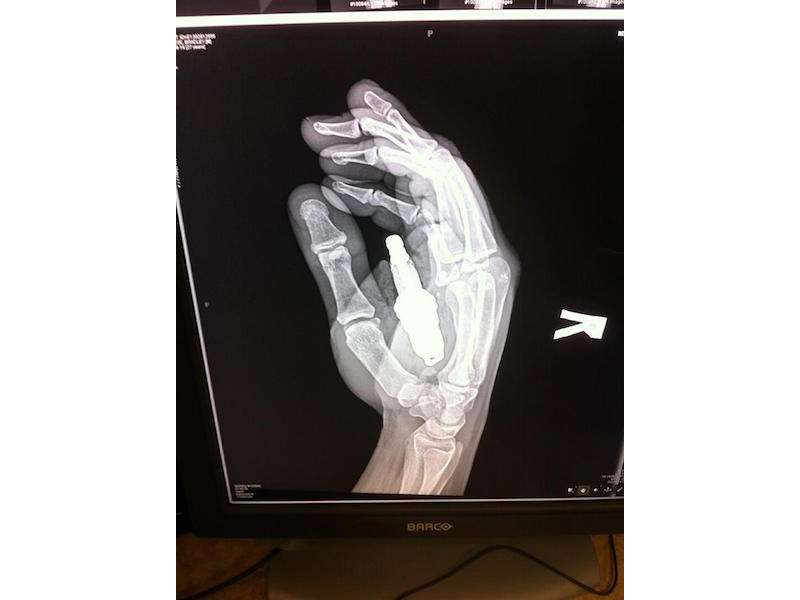

This guy, who left the hospital with the greatest x-ray of all time. Yes, that’s a spark plug lodged inside his palm. Evidently, the involved parties constructed a makeshift launching apparatus from 3/4-inch metal tubing and an air compressor. It backfired. One very messy ride to the emergency room later, the plug was extracted. Didn’t even need surgery. Hero.